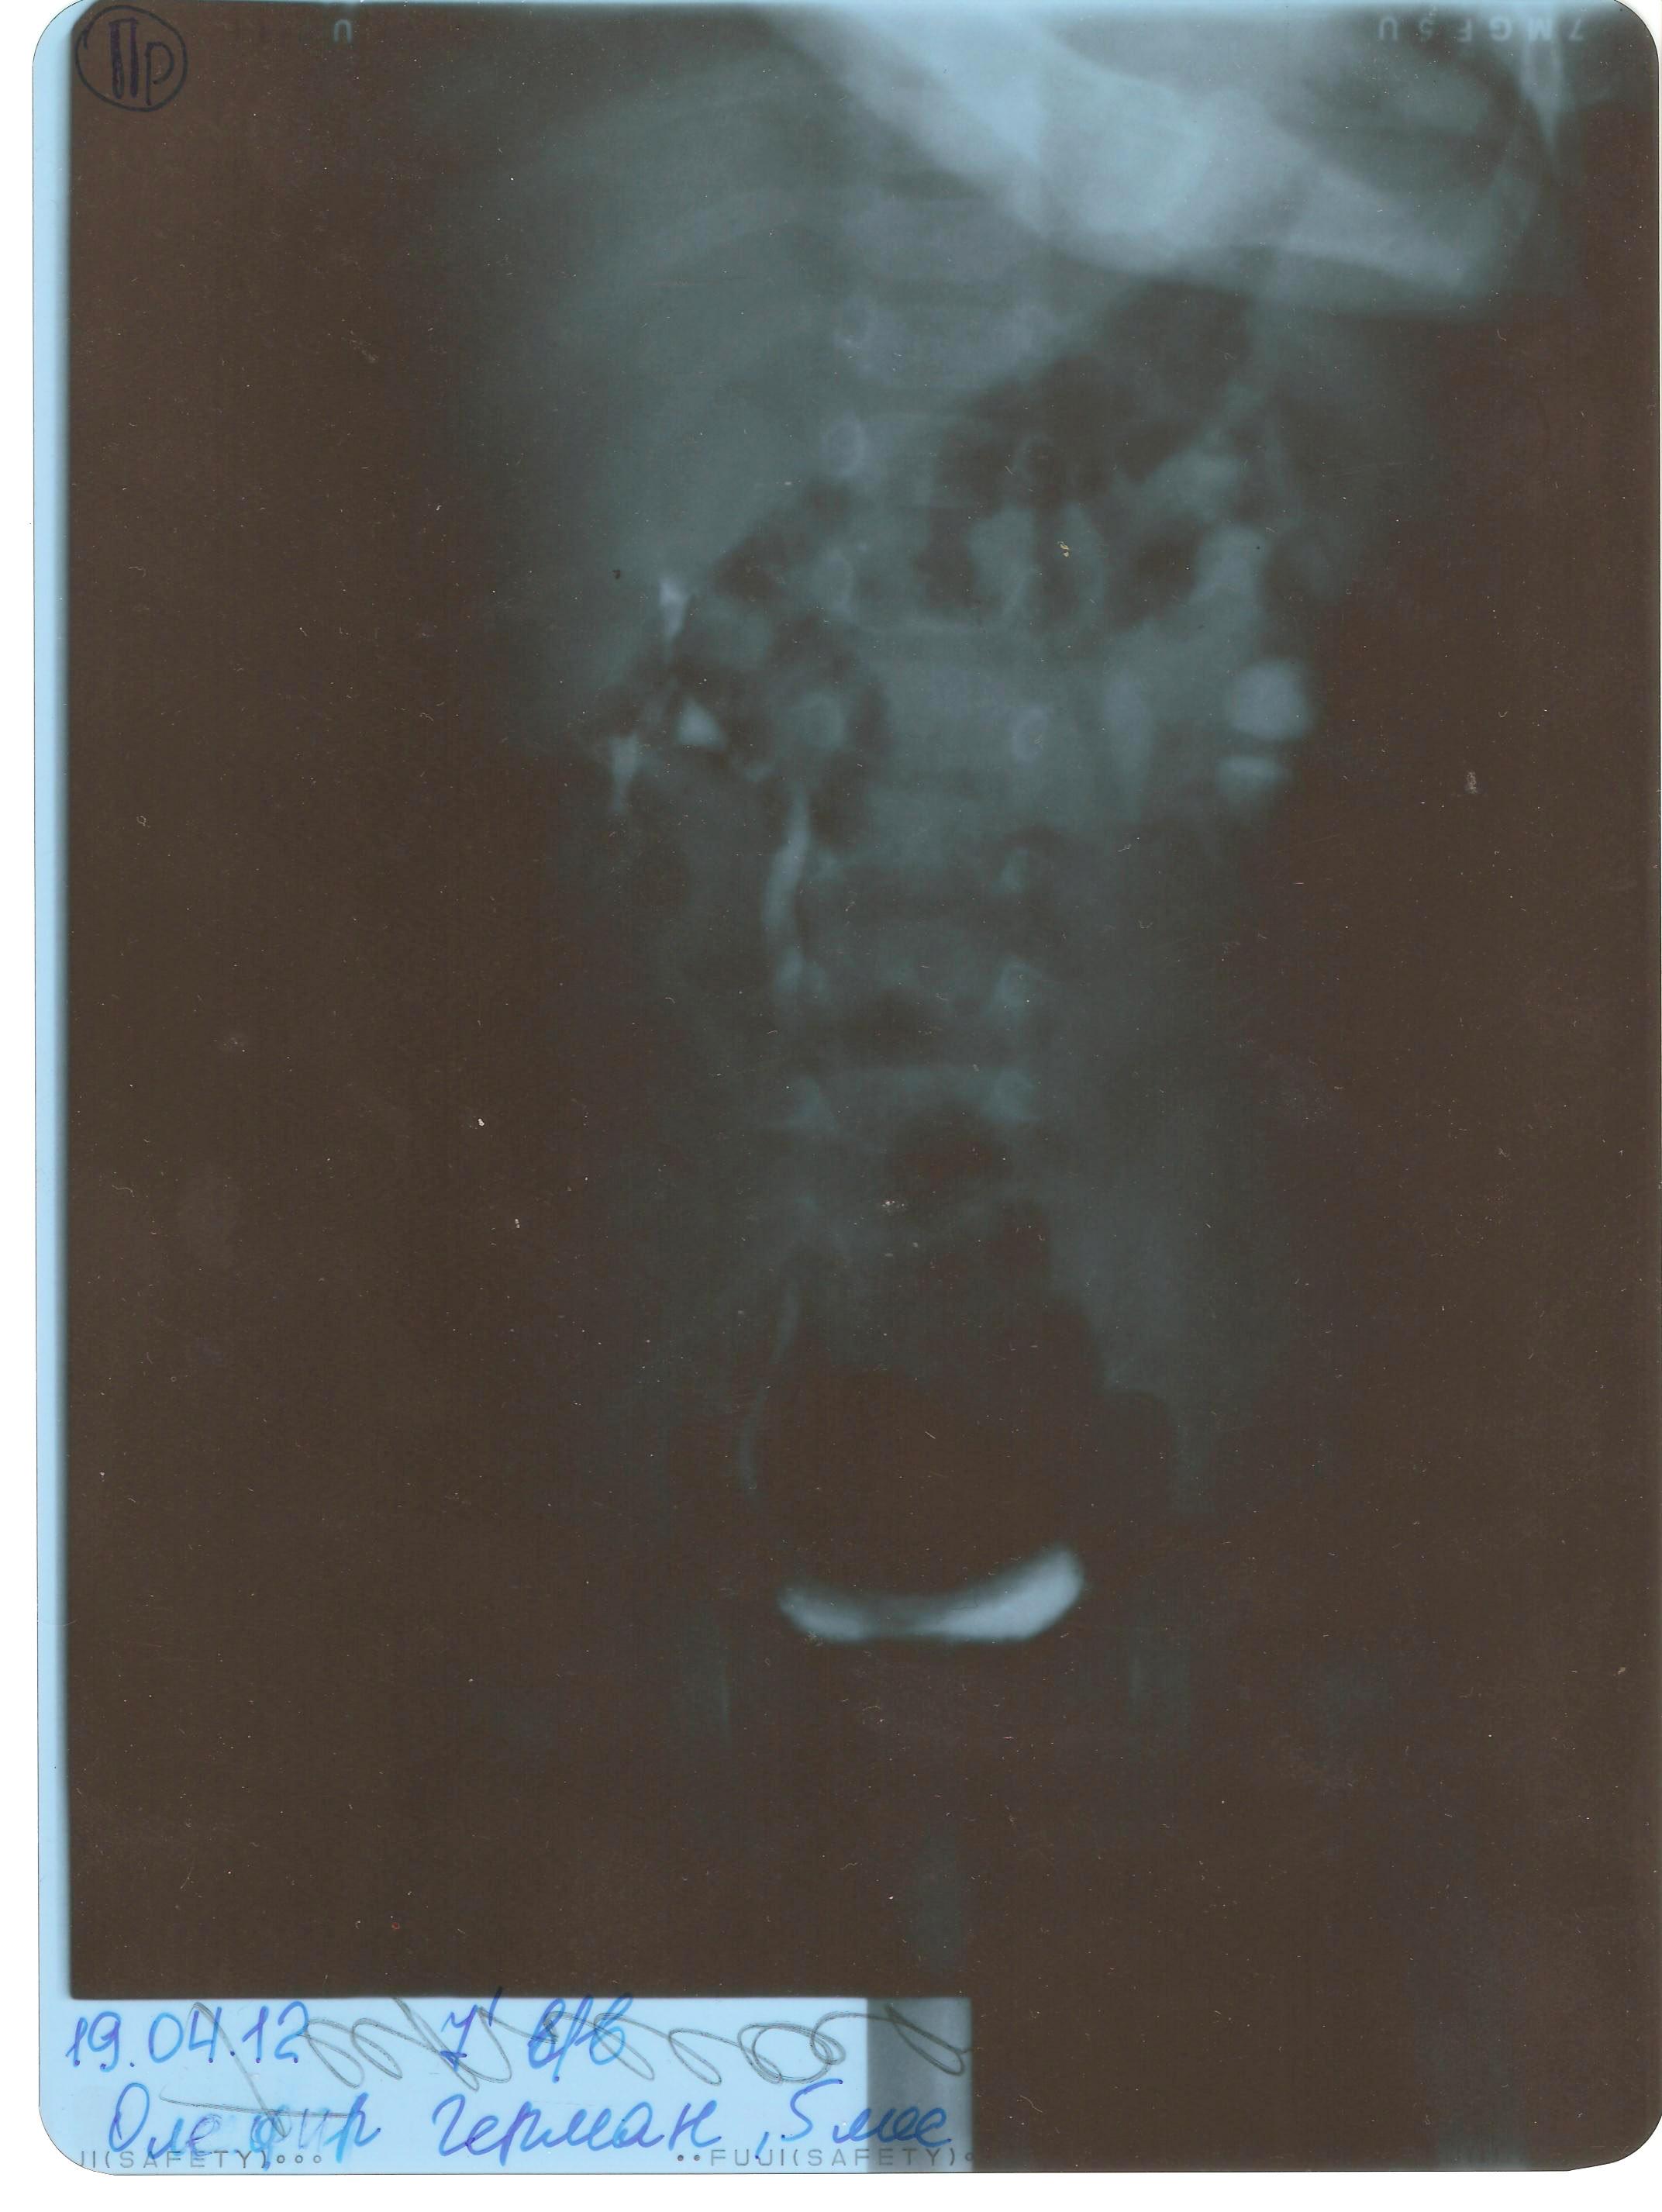

Обструктивный уретерогидронефроз слева. Есть ли показания к операции?

Вложением эпикриз и рентгенограмма с контрастным веществом. Возможно ли провести срочную КТ (компьютерная томография) диагностику в вашей клинике для определения необходимости операции?

Лучше всего - спиральная компьютерная томография. Показания к операции есть, конечно.